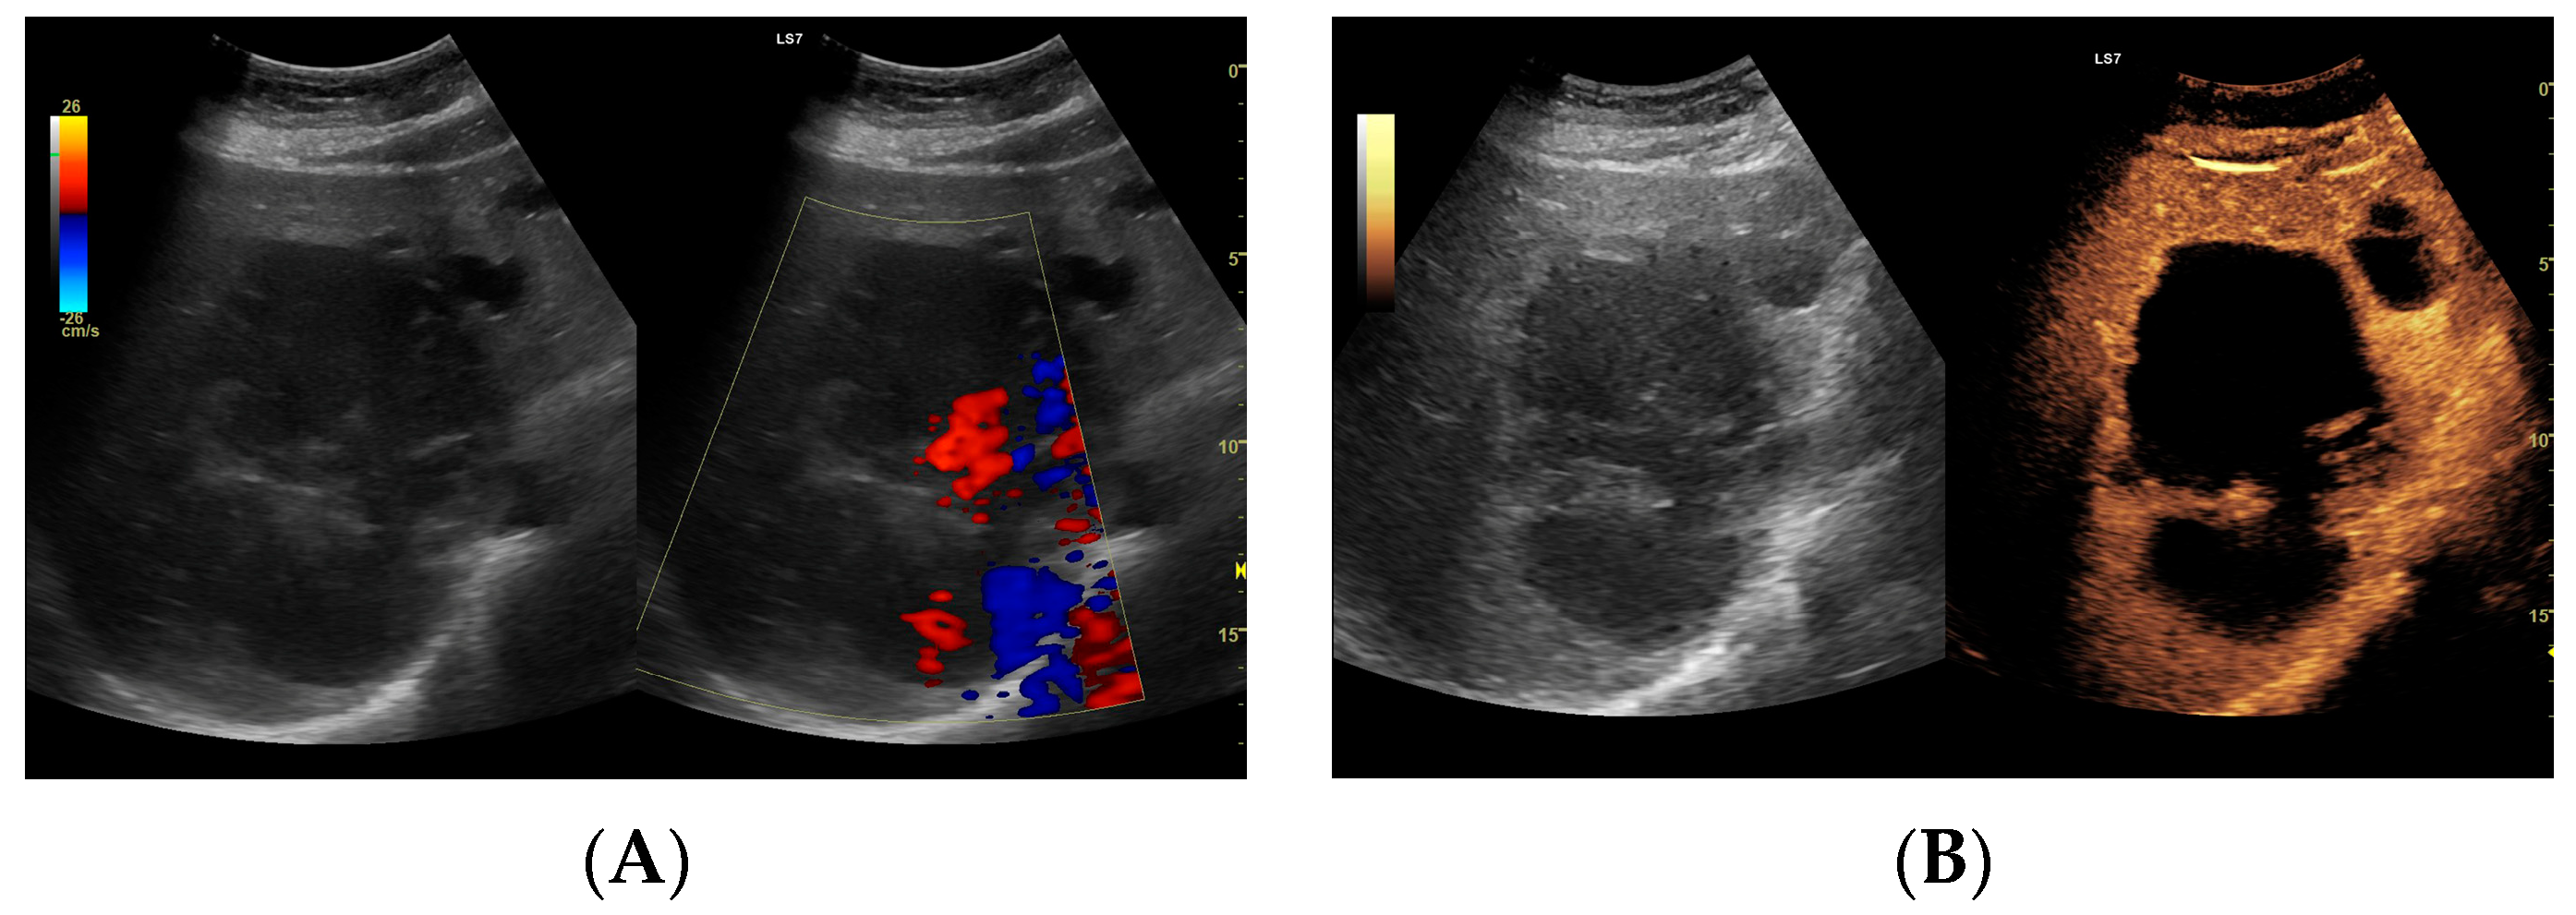

3.2.1. Arterial Phase

3.2.2. Early Venous Phase

3.2.3. Late Venous Phase